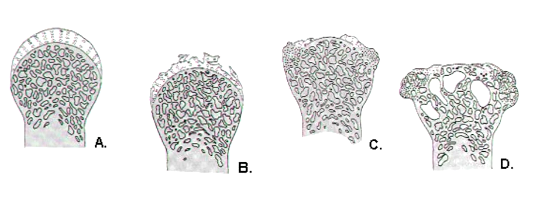

What is osteoarthritis?

What happens when bits of cartilage start to flake off in OA? How does this affect synovial membrane?

What is subchondral bone?

The layer of bone just below the cartilage in a joint